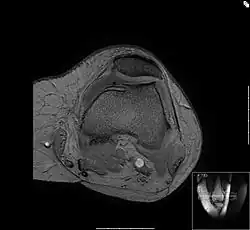

Kniescheibengelenk (Femoropatellargelenk)

Bei dem Bild „Femoropatellararthrose“ handelt sich um ein horizontales Schnittbild durch das Kniescheibengleitlager und dem unteren Ende des Oberschenkels, den Femurkondylen. Das Bild wurde mit einem NMR-Gerät erstellt. Zu sehen sind die dünne Knorpelschicht (die Kniescheibe ist nach außen verschoben), die Kniescheibengleitrinne und die Rückfläche der Kniescheibe. Diese hat mit Knochenausziehungen, den Osteophyten, auf die geänderten Belastungsverhältnisse reagiert: Der an den Knorpel angrenzende Knochen ist verdichtet.

Am Gleitlager der Kniescheibe kommt es vielfach zu einer ungleichmäßigen Lastverteilung in diesem Gelenkabschnitt. Die Streckmuskulatur des Oberschenkels kann innerhalb kurzer Zeit (14 Tage) auf eine eingeschränkte Belastbarkeit des Knies reagieren, der körpermittig gelegene Bauch dieses Muskels (Quadriceps, der Vierköpfige) verliert schnell an Kraft mit der Folge, dass die Last auf die Kniescheibenrückfläche verlagert wird.

Der Knorpel der Kniescheibenrückfläche ist mit bis zu 7 mm die dickste Knorpelschicht im Körper. Dieser Knorpel wird nicht durchblutet, sondern nur über die Gelenkflüssigkeit ernährt. Bei dieser Dicke kann das nicht mehr durch Diffusion allein funktionieren. Hier kommt ein Walkvorgang zum Tragen: Unter Last wird Synovia (Gelenkflüssigkeit) in den Knorpel hinein- und wieder herausgedrückt. Damit ist ein genügender Austausch gegeben, solange die Auflagelast im physiologischen Bereich bleibt. Das System verträgt weder zu viel noch zu wenig Druck. Weicht dieser Druck weit genug vom Idealbereich ab, kommt es zu Ernährungsstörungen des Knorpels und später zu Verschleißerscheinungen, die auch als Chondropathia patellae bezeichnet werden. Der Knorpel degeneriert, fasert auf, wird rau: Das Gleitlager der Kniescheibe fängt an zu reiben. Man spricht nun von einer Demaskierung des Knorpels. Das erste Symptom hierbei ist der Schmerz auf der Treppe, beim Aufrichten aus der Hocke oder beim längeren Sitzen. Der Volksmund nennt diese Symptome „Theaterknie“, weil sie früher bei Menschen auftraten, die nach dem ersten Akt eines Stückes mit den Füßen scharrten.